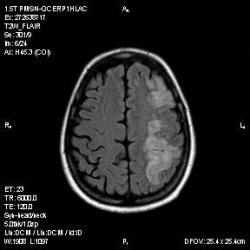

Из анамнеза - Женщина 45 лет. За год похудела на 15 кг (со слов матери), в последние месяцы случались эпизоды потери сознания. Онкозаболеваний и прочая в анамнезе нет. Сознание спутанное, из особенностей в анализах только подъем амилазы крови.

К сожалению, не владею методом КТ, но учитывая наличие неравномерного уплотнения в мозговых структурах с элементами очаговых "вкраплений", единственное, что приходит на ум - это рассеяный склероз. Хотелось бы уточнить, что беспокоило пациентку в течение последнего года кроме потери веса и эпизодов потери сознания? Была ли какая-либо очаговая неврологическая симптоматика? Отмечались ли какие-либо расстройства в двигательной или чувствительной сфере и т.д.? С уважением Helenmar.

И это точно не РС, т.к. характер очагов другой, ни один из них не копит контраст, нет субтенториальных очагов (извиняюсь, я этого в сообщении не указал), нет клиники.

"Раскрою" карты. Мы подумали о синдроме MELAS (mitochondrial encephalomyopathy, lactic acidosis and stroke) - дословно, митохондриальная энцефаломиелопатия, лактоацидоз и инсульт. В качестве дифференциальной диагностики можно было бы предположить вирусный энцефалит, но опять-таки, расположение очагов смущает - только с одной стороны и в абсолютно различных структурах.

В данном случае мы видим импульную последовательность FLAIR - режим с подавлением сигнала от воды, поэтому ликвор гипоинтенсивен, а также (вторая серия) - изображения, взвешенные по T1 после введения контрастного препарата. На T1 жидкость (ликвор) также представляется гипоинтенсивной. Зато на этих сериях гиперинтенсивны сосуды, т.к. контрастное вещество циркулирует в кровяном русле.

Изменения носят сосудистый характер. Процесс достаточно острый, имеется объемное воздействие, борозды левой гемисферы компремированы. По поводу MELAS синдрома очень сомневаюсь, почему поражена только левая гемисфера? Надо делать МР-ангиографию, смотреть нет ли стеноза

MELAS синдром - дебютирует с детских лет, характерен целый комплекс неврологических проявлений, заболевание генетическое, поражение системное, хотя есть множество вариантов митохондриального поражения, все же сомнительно. Хотелось бы акцентировать внимание, что гиперинтенсивные очаги есть в мозолистом теле, поражены выражено перивентрикулярные отделы, U -пути, белое вещество, поэтому так категорично демиелинизацию не вычеркивала бы из дифряда ( хотя тоже нетипично односторонее поражение). Думаю, для объективных выводов все же мало общей информации о пациентке, были ли клинические эпизоды раньше, чем объяснить такую потерю веса (возможно есть проявление паранеопластического синдрома?). Ну и МРТ-контроль в динамике, ангиография.

Да, неоднозначный случай. Точно не РС и не ОНМК. Я бы написала асимметричную лейкоэнцефалопатию неясного генеза. Можно было бы думать о лимфоме (полифокальное поражение, да еще мозолистое тело вроде бы задействовано (эх, сагиттальчики бы)). Но! Учитывая отсутствие накопления КВ.... Ну и надо исключать интоксикацию, всяческие аутоиммунные процессы (в т.ч. и васкулиты), сахарный диабет, ну и естественно наследственную патологию обменных процессов. УУУх! Вот.......

Имхо ишемический онмк в бассейне сма. Особенно показательны 5-й и 6-й файлы, отграничение как раз на границе бассейнов средней и перикаллёзной. Плюс одностороннее поражение.